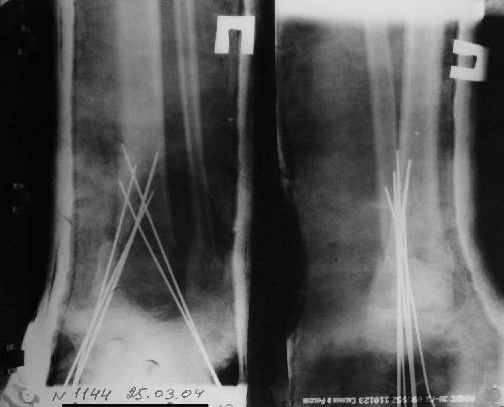

Вытяжение

|

Надо было в приемном покое отрепонировать больного и

зафиксировать б/б кость спицами крест-накрест (не обязательно двумя...

можно и 3... можно и 4... больше не нужно...)